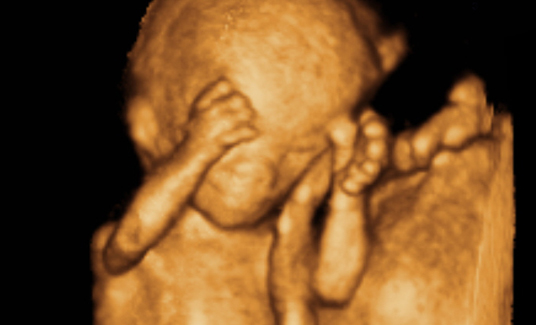

为宝宝留下成长的足迹是每一个准爸妈都想做的事情,准爸妈总是好奇宝宝在肚子里的动态,为了满足准爸妈的好奇心,安徽安琪儿妇产医院引进美国GE—E8四维彩超技术,该技术是目前国际上最先进的四维彩超技术,高清动态的显示胎儿的身体、骨骼、器官的发育情况,并通过高科技技术将宝宝的四维彩超影像刻成光盘,真正的实现零岁动态写真,可供准爸妈随时、反复的观看,为宝宝留下最珍贵的时刻。

四维彩超是目前最先进的一种彩超技术,准妈妈可以清楚的观看到宝宝的动态图像。医生也能够根据四维彩超图了解宝宝的发育情况,是否有唇裂、脑积水、畸形等异常情况,方便医生和孕妇及早的采取应对措施;根据胎儿现今的发育情况及时补充营养,更有助于宝宝的身体发育和智力发育,提高宝宝的健康指数。